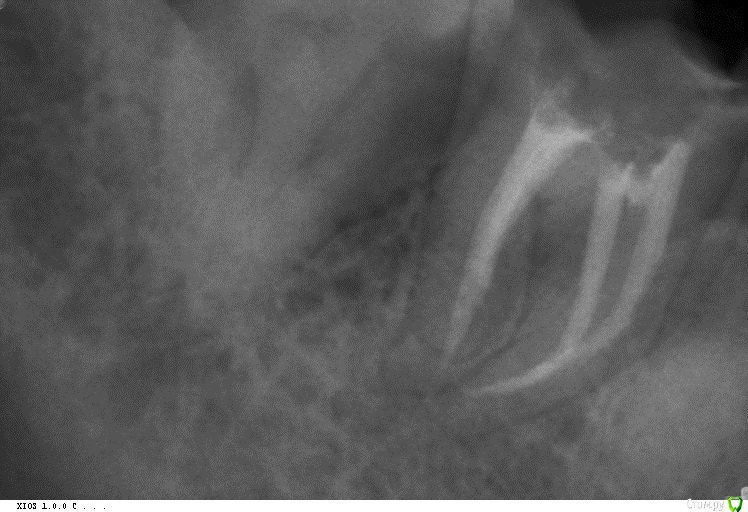

cor Опубликовано 12 марта, 2016 Поделиться Опубликовано 12 марта, 2016 (изменено) Эх, как я соскучился по К3 ! Как я их любил(люблю) только теперь у меня их нет. Там кто спрашивал по протоколу. Как это делал я, правда был молод, и имеются сомнения по поводу протокола. Думаю меня поправят достаточно оперативно, так что дождитесь, прежде чем на людях пробовать)) (пару работ скину, где до 30.04 и 30.06 в итоге на фул каналы были обработаны)Итак, опустим изоляцию, доступ,) и тд. Допустим моляр, допустим любой. Сразу скажу что размер, указанный выже всегда разный немного. МБ2 30.06 не очень мне нравиться, ну и не забываем, что руки ещё есть, что бы доработать апикальную треть. 1 Ориентировочное определение длинны - мм 16 -18 8кой(10кой) - не дошел. На эту динну работаем начиная с 30ки (04 ил 06 - по ситуации). моемся.2 Продвигаемся по аплоку на 1-2 мм - не дошли берём №25 той же конусности, или меньше, чем 30ка была.3 Опять меряем, примерно с таким же шагом, берём файл на размер меньше и идем дальше.4 Дошли до рабочей длинны, начинам работать на полную рабочую длину, в обратном порядке (размер файла растет) и мыть. 5. !!! Короче : Уменьшаем размер файла по мере увеличения рабочей длинны, затем обрабатываем на всю длину до нужного размера, но не более(обычно) 30.06. Далее апикальную треть ручками до куда вам религия подсказывает.!!! Готовлюсь морально к тапкам, которые в меня полетят)) Изменено 12 марта, 2016 пользователем cor 5 Ссылка на комментарий

cor Опубликовано 14 июля, 2016 Поделиться Опубликовано 14 июля, 2016 Для меня F3 - слишком большое расширение устьевой и средней трети. Что бы я его засунул в канал - это исключение. Меня, как и остальных, интересует апикальная треть, а именно, как добиться адекватной ирригации в ней, родимой. Можно послушать Каплана, а можно взять эндоблок, и посмотреть (Каплан, блин, прав). Протейперы, в их классическом применении не дадут Вам возможности отмыть апикальную треть, не "убивая" анатомию канала. Но протэйперы быстро и эффективно работают в других отделах канала. А именно в устьевой и средней трети.Дальше можно подключить другие инструменты. Будь то профайлы, а может и К-3. Готовясь к "тапкам" опубликую ленивый протокол. Он работает только с опытом его использования, и пониманием, зачем)) По протоколу до протейпера F2, 30.06 профайл (35.04,40.04, 45.04 - по ситуации). Обязательно апикальный упор (калибровка гутты обязательна, только "2 конус). Ну и опыт в таких "экспериментах" заканчивался латералкой. Было здорово. Но попробуйте на удалёнках сначала, а то Мяуздрав предепреждает)) Ссылка на комментарий

Audutor Опубликовано 14 июля, 2016 Поделиться Опубликовано 14 июля, 2016 (изменено) Для меня F3 - слишком большое расширение устьевой и средней трети. Что бы я его засунул в канал - это исключение. Меня, как и остальных, интересует апикальная треть, а именно, как добиться адекватной ирригации в ней, родимой. Можно послушать Каплана, а можно взять эндоблок, и посмотреть (Каплан, блин, прав). Протейперы, в их классическом применении не дадут Вам возможности отмыть апикальную треть, не "убивая" анатомию канала. Но протэйперы быстро и эффективно работают в других отделах канала. А именно в устьевой и средней трети.Дальше можно подключить другие инструменты. Будь то профайлы, а может и К-3. По протоколу до протейпера F2, 30.06 профайл (35.04,40.04, 45.04 - по ситуации). Обязательно апикальный упор (калибровка гутты обязательна, только "2 конус). Ну и опыт в таких "экспериментах" заканчивался латералкой. Было здорово. Но попробуйте на удалёнках сначала, а то Мяуздрав предепреждает)) Если мы говорим о геометрии инструмента, F3 протайпер единственный инструмент подобного размера с измененной геометрией в апикальной трети для лучшей ирригации, а имено 9% конусность в 3х апикальных миллиметрах, и 6% в остальной части, выходит он лучше прочих подходит для дезинфекции именно апикальной трети. Кстати вы в курсе что профайлы продаваемые именно в Европе на самом деле имеют геометрию и размеры отличные от официально заявленных? 30 размер к примеру это примерно 29 итдБыла даже гдето специальная статься наэту тему. В случаях сложной анатомии само собой я беру в руки, Pathfile и профайлы 4 конусности итд итп П.С Практически все лекции российских специалистов это перефразирование зарубежных коллег с задержкой в месяцы, года) Но видео посмотрю) П.П.С В любом случае 30-40 минут дезинфекции с активацией никто не отменял) П.П.П.С corВаша методика это crown down плюс примесь balanced force. Изменено 14 июля, 2016 пользователем Audutor Ссылка на комментарий